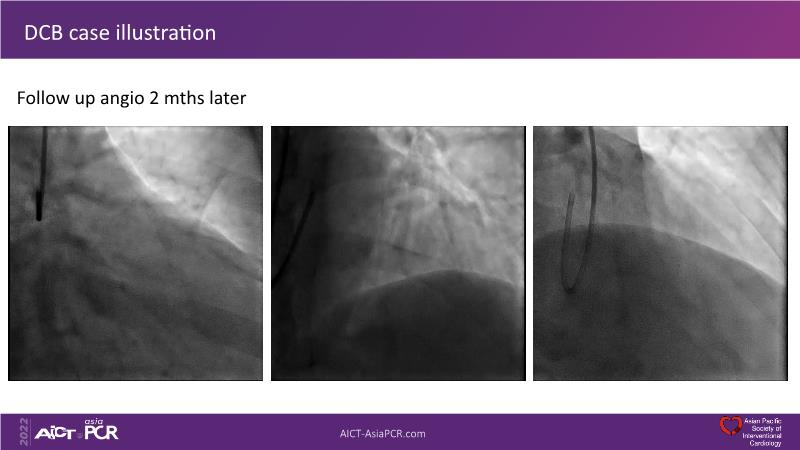

Consult this session to understand the technology and scientific evidence of the novel sirolimus drug-coated balloon, to learn its utility for PCI in a variety of lesion and patient subsets and to understand the evidence and outcomes in real-world patients.

- To learn the utility of the DCB for PCI in a variety of lesion and patient subsets

- To understand the evidence and outcomes of this DCB in real world patients